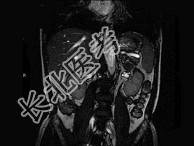

- 单项选择题男,52岁, 下肢无力伴多饮多尿2年余,实验室检查: 低血钾,血醛固酮水平及24小时尿醛固酮定量超过正常值, MRI检查如图所示,应诊断为 ( )

A、左肾上腺囊肿

B、左肾上腺腺瘤

C、左肾上腺嗜铬细胞瘤

D、左肾上腺髓脂瘤

E、左肾上腺转移瘤